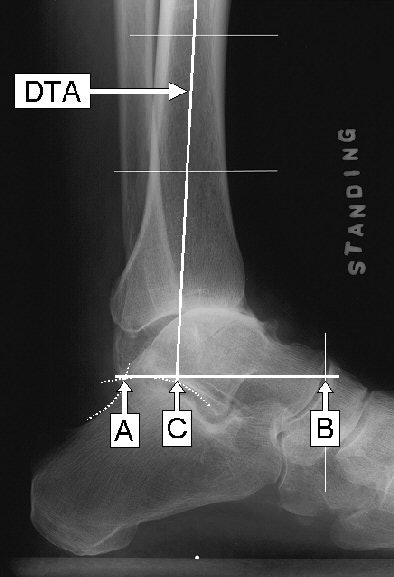

The authors calculate the TT ratio as a percentage equal to AC divided by AB times 100 (TT ratio = AC / AB x 100). In one typical example given at the AAOS, the TTR calculated out as 55.3%.

Point A is the posterior talar point, or the intersection between the contours of the posterior subtalar articular surface and the posterosuperior calcaneal cortex. Point B is the anterior talar point, or the vertical projection of the most anterior aspect of the talus onto the talar reference line.

The talar reference line is a line through point A parallel to the floor. The longitudinal talar length is AB. The distal tibial axis is the longitudinal midbisecting line of the tibial shaft determined at 5 cm and 10 cm above the ankle, and its intersection with the talar reference line is point C.

| TT ratio = AC / AB x 100. The superimposed letters on this radiograph show the locations for measurements to calculate the tibial-talar ratio of anteroposterior ankle alignment. Image courtesy of Dr. Yuki Tochigi. |